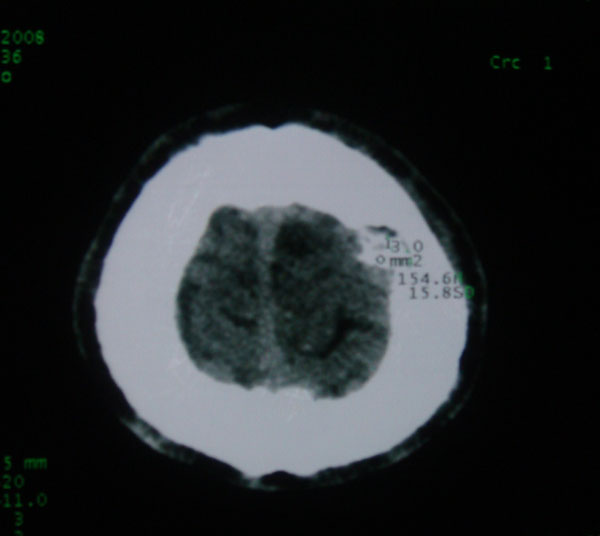

以下是引用拾荒者在2008-6-7 13:05:00的发言:[br]左侧顶骨局限性骨质缺损,边缘锐利,无硬化边,周围软组织轻度肿胀,无明显软组织肿块及骨膜反应,考虑嗜酸性肉芽肿可能。